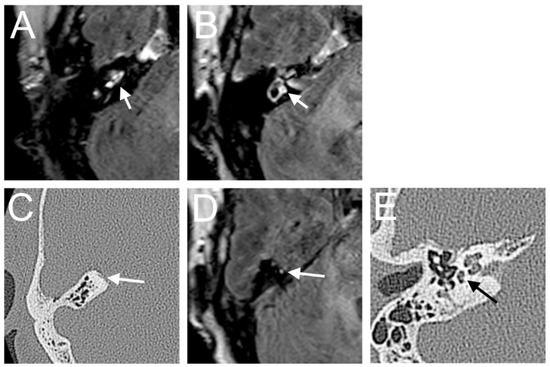

A 48-year-old male presented with a sudden hearing loss on the right side with tinnitus. He showed no vestibular symptoms. The PTA was 110 dB on the right side. Intraoperatively, a PLF track around the RW niche was observed, and the CTP on the right side was positive. A normalized signal intensity of the vestibulum and cochlear was observed on T1W and CE-T1W. A hyperintense signal intensity was found on T2-weighted MRI sequences. On the 4 h delayed 3D-FLAIR image, a contrast enhancement was found in the cochlea, vestibulum, and fundus on the right side of the ear with hearing loss (Figure 3A,B). An RWS was not detected in the affected ear. In this MR sequence, we could also observe a SURI on the right side (vestibular endolymphatic hydrops, grade I) (Figure 3C).

A 77-year-old male was referred to our emergency unit because he first developed a sudden hearing loss on the right side with rotatory vertigo but without tinnitus. On examination, a left spontaneous nystagmus with horizontal and torsional components was noticed. The nystagmus decreased during eye fixation. The PTA was 110 dB on the right side. The VHIT showed a decreased VOR gain of the left posterior (0.26) canals, whereas the other VOR gain was preserved (>0.85). The cervical VEMP was absent on both sides. Moreover, a profound canal paresis on both sides was observed with caloric tests. There were clinical signs assuming a PLF intraoperatively, but the CTP was negative. The contrast enhancement was seen in the right cochlea (Figure 5A) and vestibulum (Figure 5B) on the delayed postcontrast 3D-FLAIR sequences. In the computed tomography, a dehiscence in the right superior semicircular canal was detected, which could also be confirmed as an MR enhancement in that area on the delayed postcontrast 3D-FLAIR sequences (Figure 5D). A hyperintense signal was shown in the left cochlear on the T1 sequence. About 1/3 of the fluid filling in the RW niche was observed in the CT, but in the T2W MRI, none of the fluid fillings were detected.

Figure 3. A 48-year-old male presented with a sudden hearing loss on the right side with tinnitus. The axial 4 h delayed 3D FLAIR sequence shows a contrast enhancement in the cochlea basal turn on the right side (A). In the same MR sequence, a vestibulum (arrow (B)) and fundus (dashed arrow (B)) and MR enhancement were observed, as well as an inversion of the saccule (arrow (C)) and utricle (dashed arrow (C)) area ratio.

Figure 5. A 77-year-old patient with sudden hearing loss on the right side with rotatory vertigo. The contrast enhancement was seen in the right cochlea (A) and vestibulum (B) on the axial delayed postcontrast 3D-FLAIR sequences. In the axial CT image, a dehiscence in the right superior semicircular canal was detected (C), which could also be confirmed as a nodular contrast enhancement (array) in 4 h delayed 3D-FLAIR sequences (D). About 1/3 of the fluid filling in the RW niche was observed on the axial CT (E).